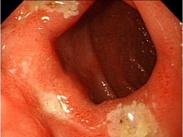

病毒性食管炎

628健康網為您分享有關病毒性食管炎的癥狀,病毒性食管炎的治療方法,病毒性食管炎的預防知識,病毒性食管炎的癥狀圖片,病...